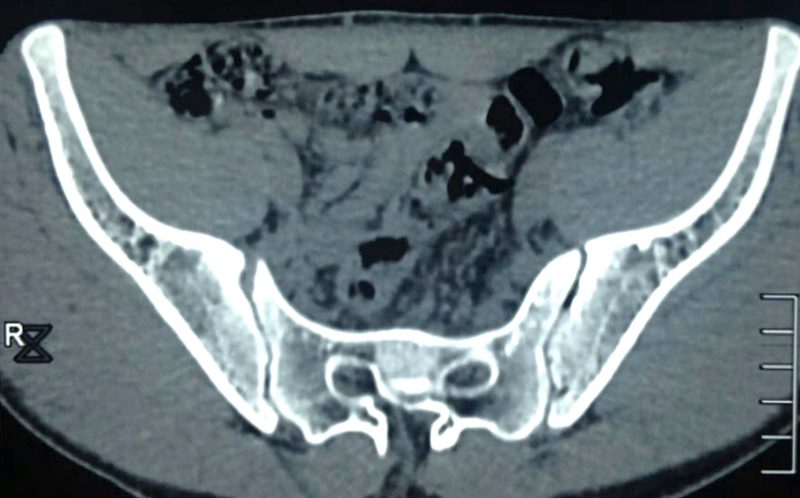

由于男孩的“尾巴”内已开始形成骨骼,切除时会触及部分脊髓,因此由神经外科医生主导。手术很成功,这条“尾巴”被顺利地切除下来。

“人尾”的形成原因复杂,可能与发育或非发育情况相关,如神经管闭合不全、脊柱裂、脊椎栓系综合征、脂肪瘤等。一项研究显示,腰骶部凸起物的成因主要包括:脂肪瘤(67%),畸胎瘤(25%)及脊膜膨出(4%)。为了确定治疗方法,进一步的影像学检查通常是必要的。